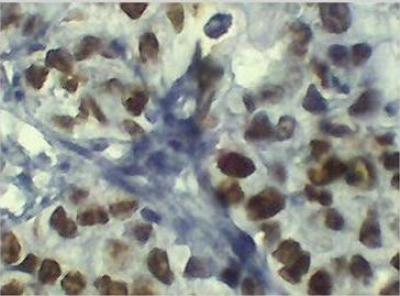

Figure 1: Positive (IHC) detection of p53 protein (A-D). Tissue with crisp brownish nuclear precipitatation of p53 protein overexpression; (A) S0045164, magnification x40, (B) S004776, magnification x10. (C) S0048960, magnification x10, and (D) S0047962, magnification x40